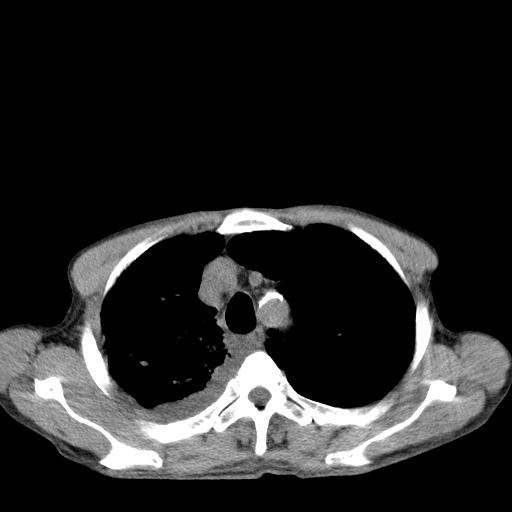

男性 75  咳嗽 一周前发热最高达39

右肺继发型tb并右侧tb性胸腔炎,右侧胸腔大量积液并右下肺膨胀不全,慢支肺气肿、多发肺大泡。建议抽胸水实验室检查并复查排除恶性在占位。

右上肺继发型肺结核,右胸腔中等量积液。

左上肺大泡。

结核的基础上有纵隔淋巴结肿大,右侧有胸水,但右侧纵隔反而窄,说明有肺有不张。

再就是右下肺有块影,和不张混合,还是不能除外肺癌。

补充材料,患者2月份ct片大致正常,双侧胸腔积液,2月份抽胸水未发现ca细胞,现患者发热,痰多,各气管通畅,

1)右肺继发型肺结核。2)左肺胸膜下多发性肺大泡。3)右侧胸腔积液。